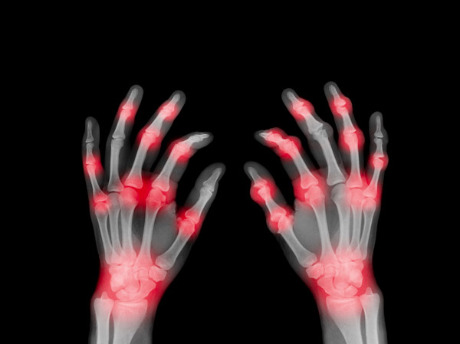

Rheumatoid arthritis is an autoimmune disease where the immune system mistakenly attacks a person’s joint tissues, causing inflammation and pain. It is a complex disease that develops as a result of interactions between a combination of genetic and environmental factors.

Figure 1: Rheumatoid arthritis occurs when the immune system attacks joints causing inflammation. Scientists now have a better understanding of the genetics underlying the condition, thanks to a genome-wide association analysis that drew on data from people of five different ancestries. © Peter Dazeley/The Image Bank/Getty Images